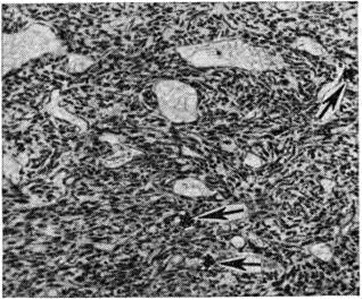

Дифференцированная Гемангиоперицитома встречается редко, может возникать в любом возрасте, часто у детей. Как правило, характеризуется медленным ростом, обычно достигает крупных размеров, сохраняя при этом чёткие контуры и подвижность. Локализуется преимущественно в коже, мягких тканях туловища и конечностей, реже — в забрюшинном пространстве, средостении, сальнике, языке и внутренних органах (печень, кишечник, мозг и другие.). Макроскопическое строение — опухоль узловатой формы, на разрезе розовато-красного цвета, пористого строения, с обилием подходящих к ней сосудов. Микроскопически характеризуется большим количеством капилляров, выстланных эндотелием и окружённых округлыми, овальными или веретенообразными клетками с темными ядрами и светлой цитоплазмой (рисунок 1). Клетки оплетены густой сетью аргирофильных волокон. Основным отличием Гемангиоперицитома от капиллярной ангиомы является массивная пролиферация периваскулярных клеток, которые большинство исследователей относит к перицитам. Дифференцированные Гемангиоперицитома, как правило, отграничены от мягких тканей слоем гиалинизированной ткани, которая, однако, на многих участках проращена опухолевыми клетками, что свидетельствует о местнодеструирующем росте. Дифференцированные Гемангиоперицитома являются потенциально злокачественными опухолями, так как обладают высокой склонностью к рецидивам после недостаточно широкого хирургического иссечения. В редких случаях дифференцированные Гемангиоперицитома могут давать отдалённые метастазы. Недифференцированная Гемангиоперицитома (синонимы: гемангиоперицитарная саркома, перителиальная саркома, перителиома, периэндотелиома) является злокачественной опухолью. На ранней стадии развития недифференцированную Гемангиоперицитома клинически и даже на основании морфологически исследования бывает трудно отличить от дифференцированной. Опухоль встречается редко, локализуется преимущественно в мягких тканях конечностей, реже в забрюшинной клетчатке, внутренних органах, костях. |

Рис. 1. | ||